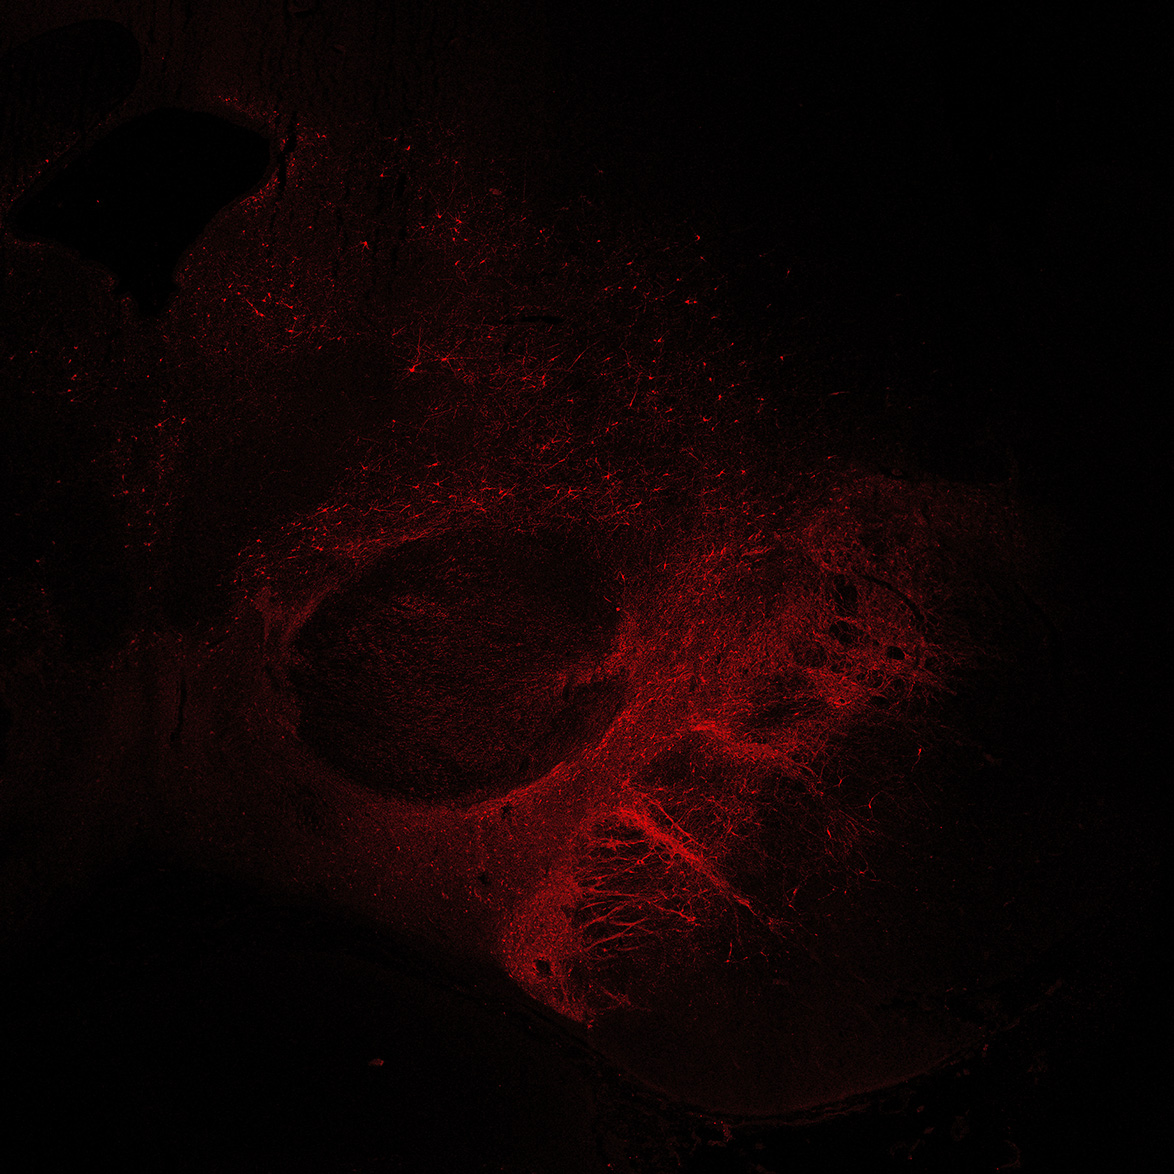

TH

11PCW human midbrain